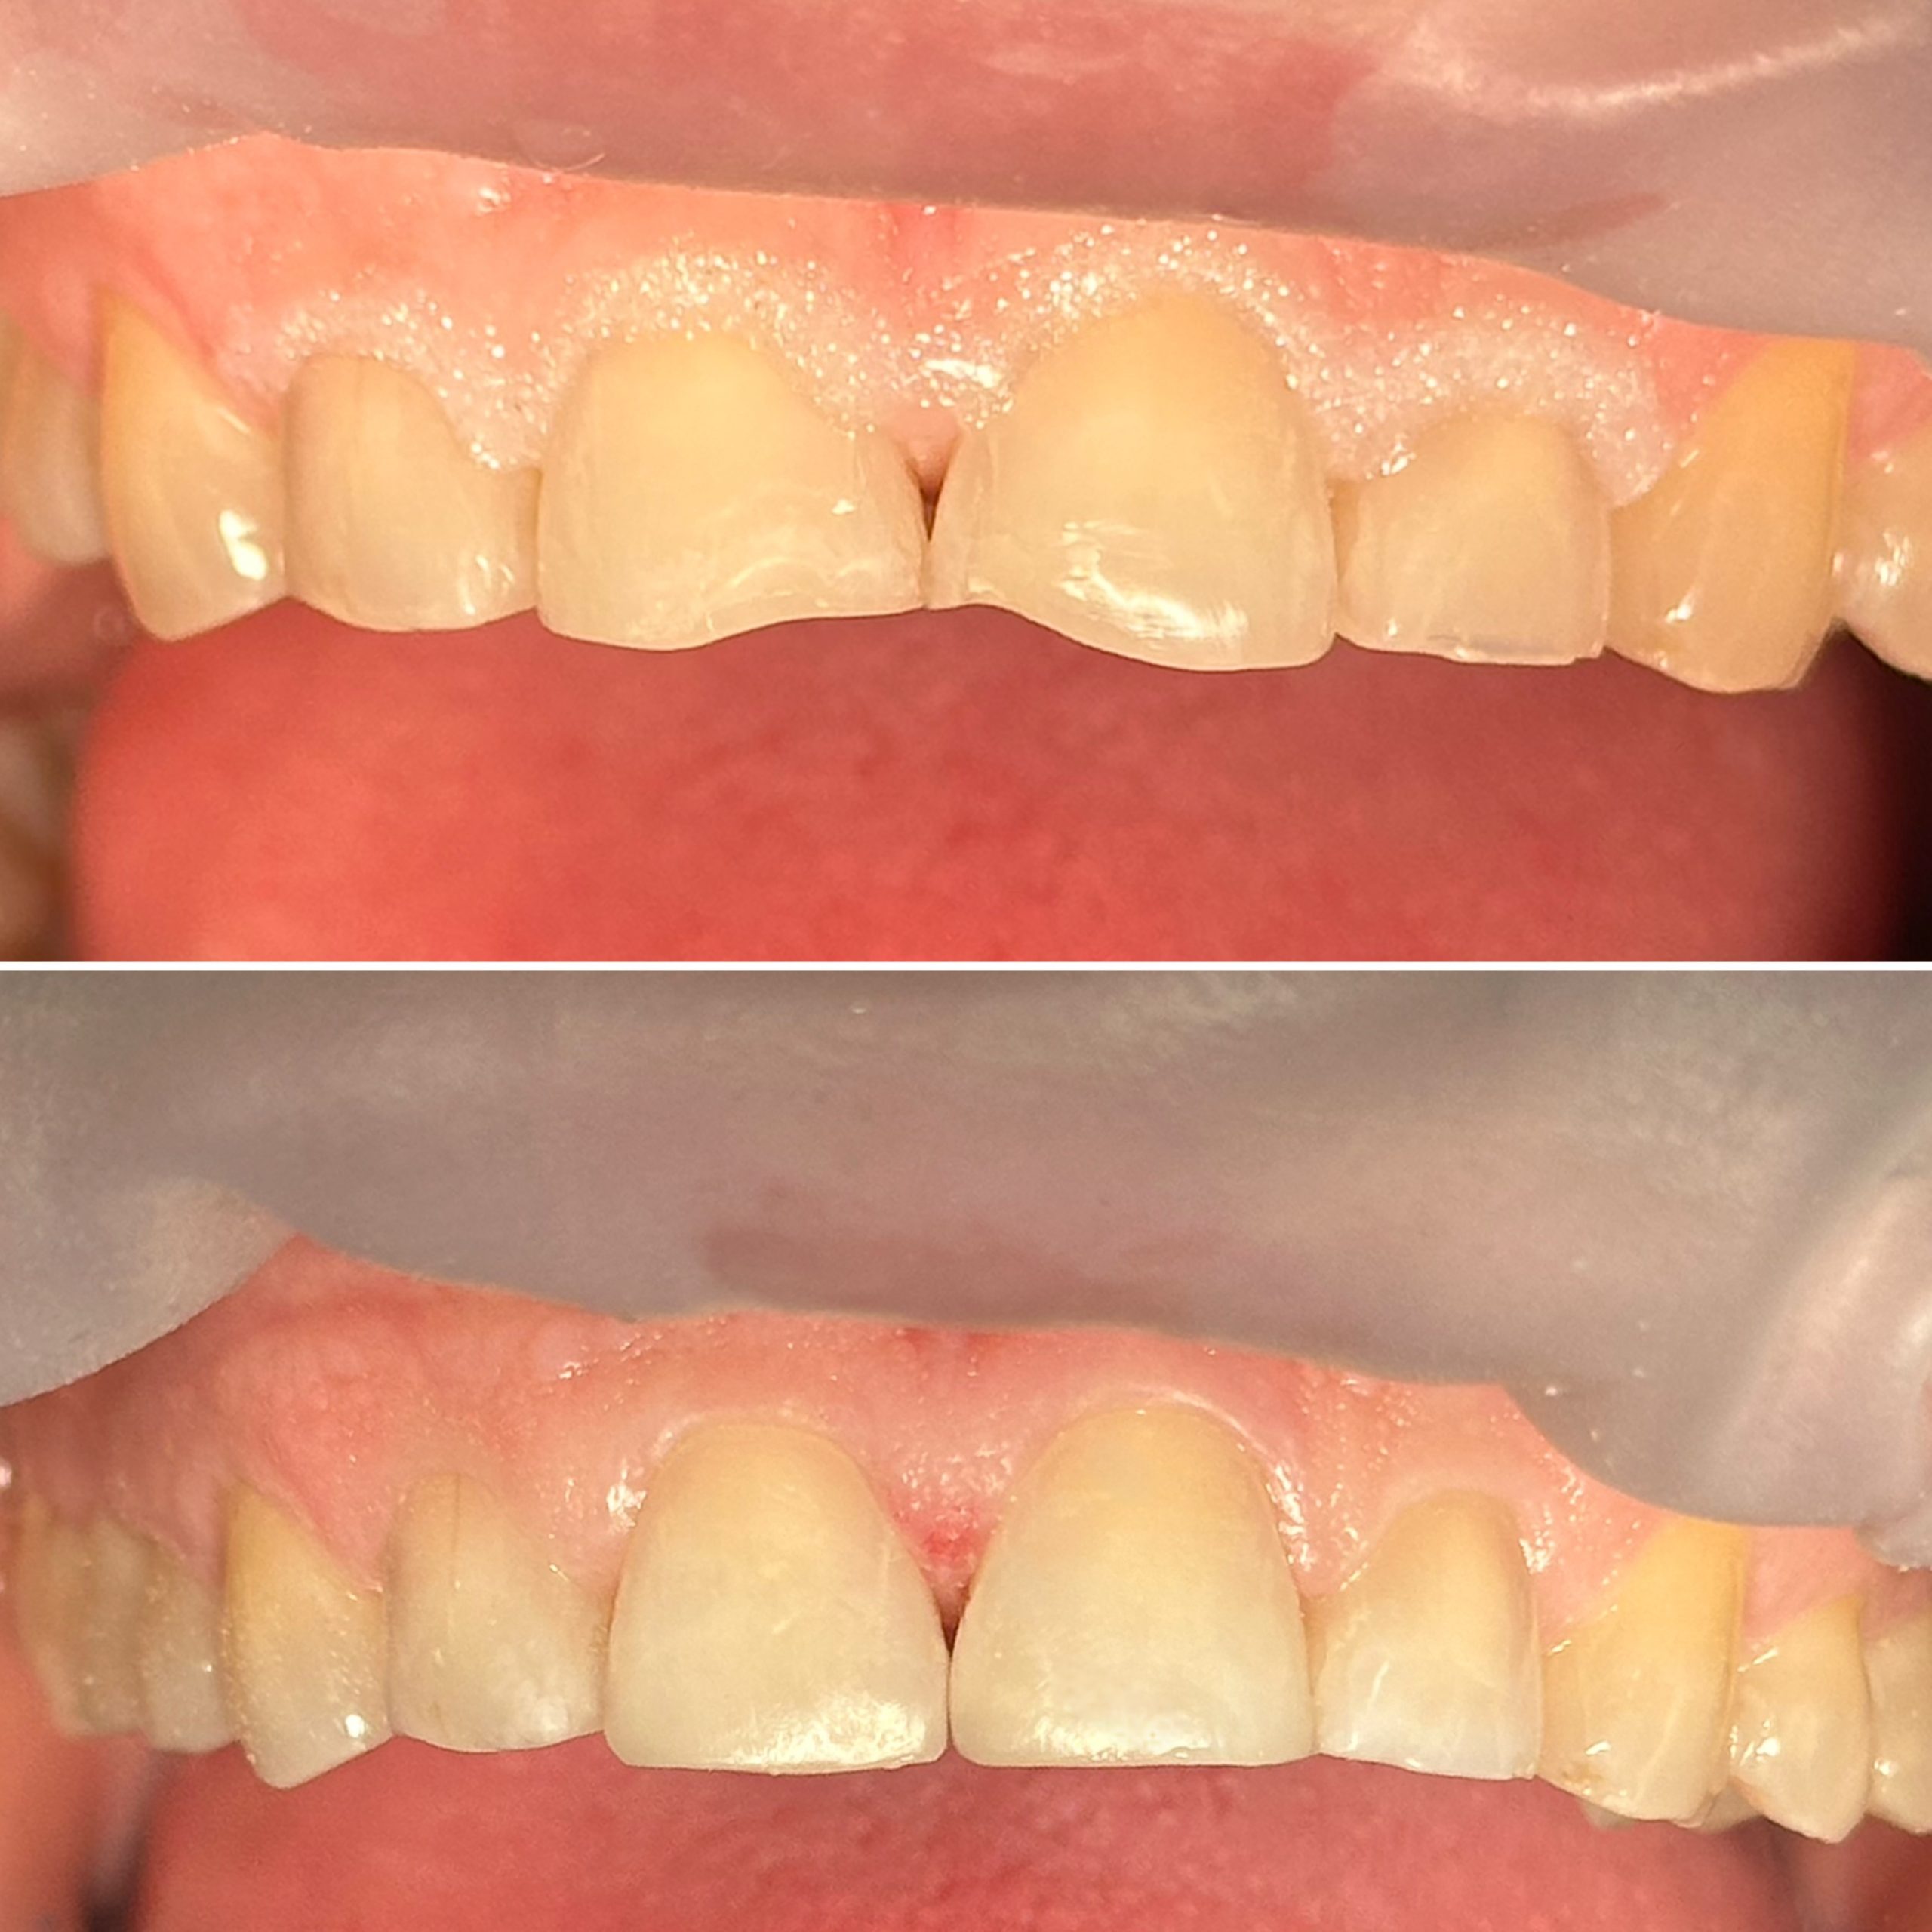

• Художественная реставрация фронтального и бокового участка зубов

2023 год – «Прямая композитная реставрация фронтальной группы зубов» Владимир Мальченко